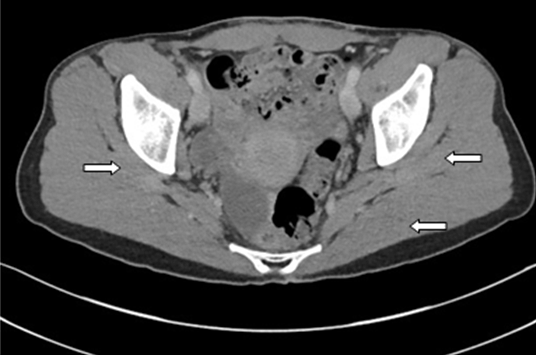

The patient was started on a regime of intravenous amoxicillin (1 gram tid for 6 weeks) followed by oral amoxicillin 1 gram tid for six months. She responded well to amoxicillin and gradually symptoms abated. After six weeks of antibiotic therapy, follow-up CT scan revealed two small fluid collections, which were most likely post-operative and did not warrant drainage. Further notable improvement was noted at sixth-month follow-up visit via computed tomography scan (Figure 4) and (Figure 5).

Figure 5: Coronal computed tomography imaging of patient, six months into treatment. The infection, previously present in the ovaries and pelvis, has resolved.